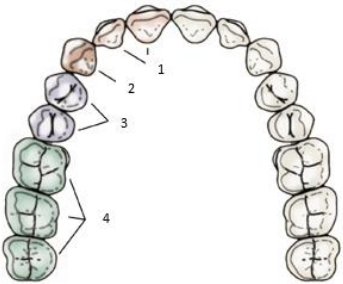

Sobre a nomenclatura da dentição decídua, analise a afigura e estabeleça a numeração correta:

Arco dental superior

A sequência CORRETA é: